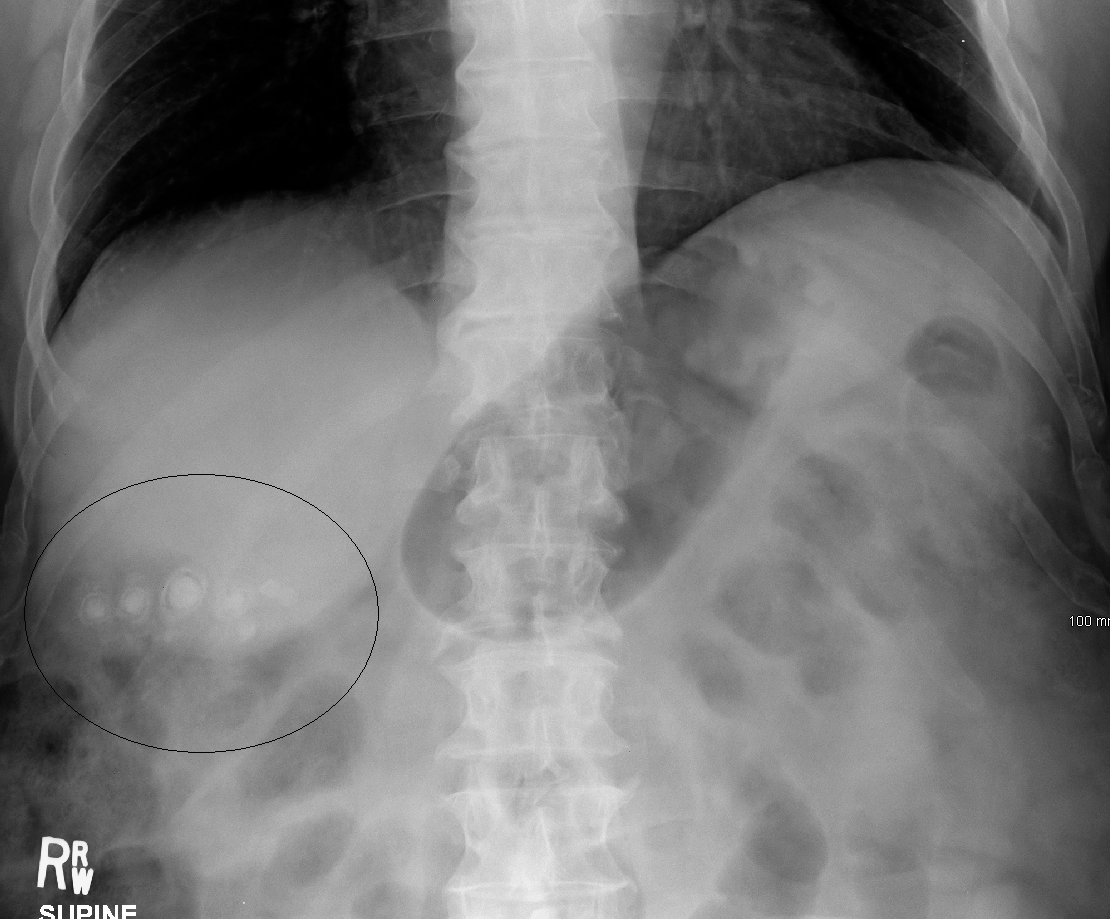

단순 X-ray에서 보이는 담석